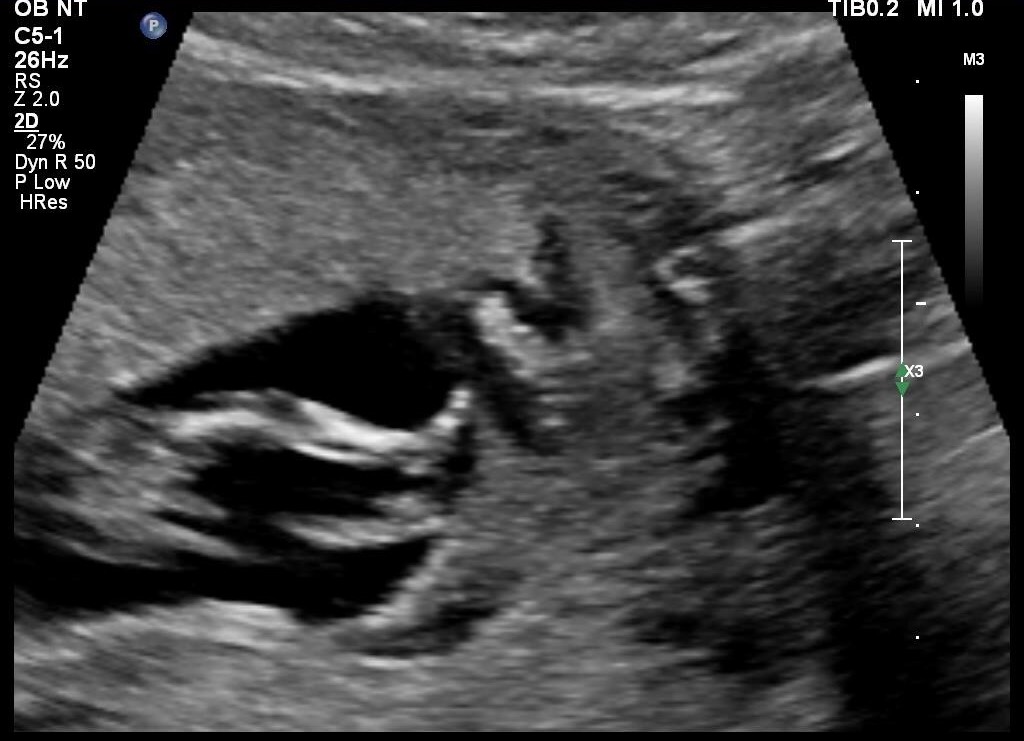

Attachment 30322

I am def not an expert but the top one looks girly while the bottom one looks like a boy! Sorry - probably the least helpful reply ever... I hope you hear boy x

The third pic looks like the nub is angled if that's the nub there so going to guess boy. Hope I am right for you. Good luck at the next scan xx

First pic looks like girly. But last one is a bit angled.